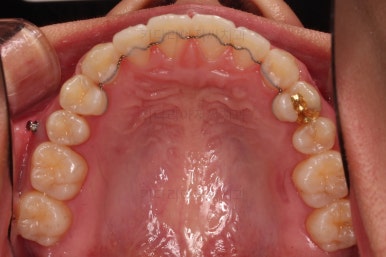

장치를 부착했는데요.

윗니는 웃을 때 더 많이 보이기 때문에 세라믹 장치를 선택하셨고, 아랫니는 거의 안보이는 타입이셔서 메탈장치로 부착을 했습니다.

위아래 둘 다 자가결찰 장치였고요.

동일 회사의 장치였으며 단지 재질만 메탈이냐 세라믹이냐의 차이가 있었던거죠.

우선 가지런하게 하는 작업을 했고요.

교합을 맞춰야 하기 때문에 윗니는 통째로 약간 뒤로 밀어줍니다.

그래서 위아래 좌우 모두 다른 용도로 미니스크류가 식립되었고요.

각각의 방향으로 계속 당겨줍니다.